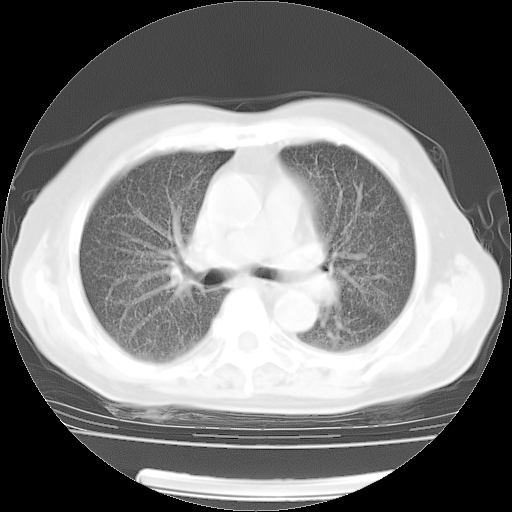

4月14日肺部CT

23.JPG

24.JPG

25.JPG

26.JPG

肺部CT平扫未见异常。